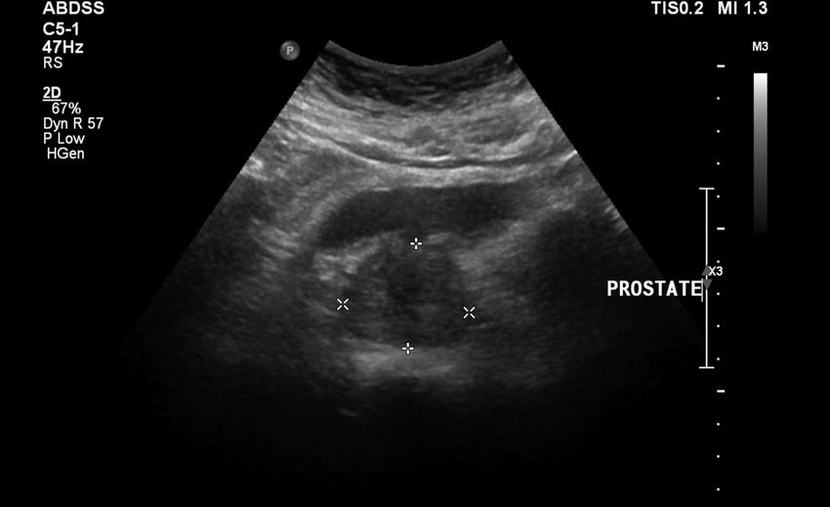

Nisu pustili da gumirani žive mirno, a zatim je dodana bolova u donjem dijelu leđa, testovi i rezultati ultrazvuka bili su loši. Bilo je doslovno nemoguće odmaknuti se od WC -a, bilo je osjećaja težine u preponama i stalne boli. Propisana je izravna masaža prostate, što me je uguralo u paniku. Počeo je tražiti druge, manje traumatične metode izlječenja.